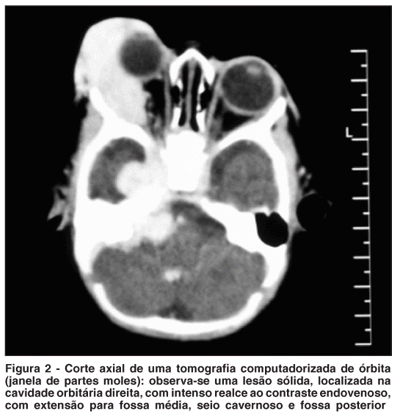

O exame de tomografia computadorizada de órbita e crânio (Figura 2) mostra a presença de uma lesão expansiva, vascularizada ocupando a cavidade orbitária direita, causando proptose do globo ocular direito. Esta lesão estende-se para fossa média, seio cavernoso e fossa posterior. Observa-se a presença de uma lesão com características semelhantes e menores dimensões na topografia do IV ventrículo. Após investigação sistêmica, a presença de hemangiomas viscerais foi descartada.